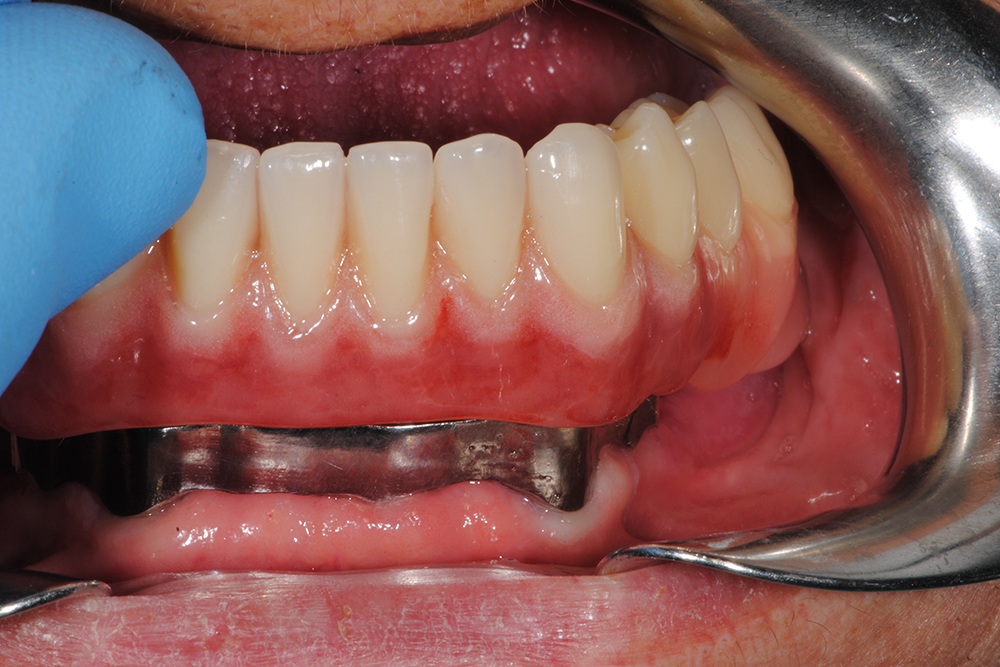

Ripristino dell’arcata superiore ed inferiore su overdenture su barra